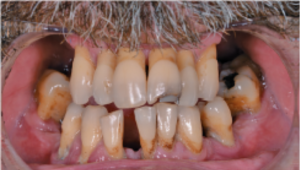

a. Situación clínica inicial del paciente con compromiso periodontal avanzado y movilidad severa de las piezas dentales. Evaluación radiológica previa al tratamiento para el análisis del volumen óseo y la planificación de implantes.